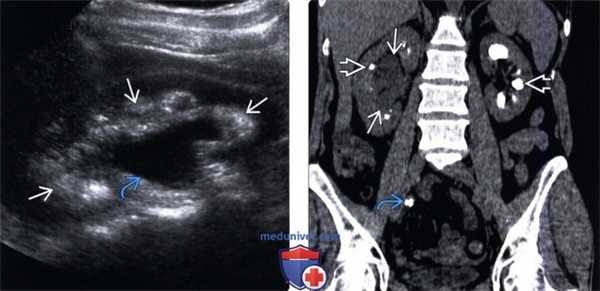

(Левый) На продольном ультразвуковом срезе почки с гидронефрозом средней степени визуализируется гиперэхогенное мозговое вещество — признак нефрокальциноза -заболевания, предрасполагающего к образованию конкрементов в почках.

(Правый) На фронтальном реформатированном КТ срезе без контрастирования у того же пациента подтвержден нефрокальциноз с множественными двусторонними конкрементами и правосторонний гидронефроз средней степени, вызванный обтурацией конкрементом правого мочеточника.

(Левый) На продольном УЗ срезе трансплантата почки визуализируется дилатация почечной лоханки и чашечек, обусловленная протяженной стриктурой мочеточника.

(Правый) В MIP-режиме КТ антеградной нефростомографии у этого же пациента визуализируется тяжелый гидронефроз трансплантата почки. Имеется протяженная фиброзная стриктура мочеточника трансплантата. Требуется хирургическая реконструкция.